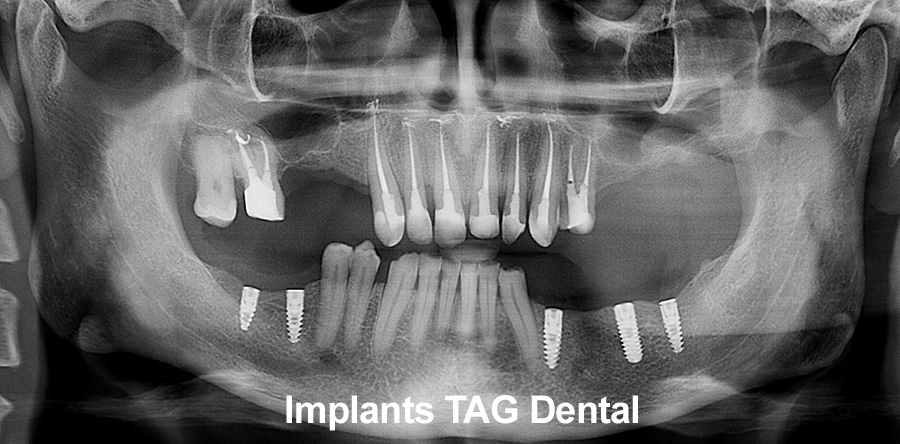

Рентген имплантов Alpha Bio: диагностика и качество